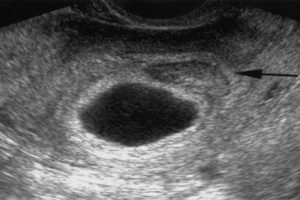

Для того чтобы обнаружить проблему, врачу необходимо будет использовать ультразвук. Некоторые считают, что отслойка яйца – это вполне естественное явление. При здоровом и сильном плоде есть большая вероятность того, что он сохранится, и будет развиваться дальше.

Плодное яйцо обнаруживают на УЗИ в виде небольшого пузырька, обычно на 4-6 неделях беременности, а его размеры считаются главной характеристикой. Нормальное развитие может замедлиться из-за различных патологий. Чаще всего встречается отслойка, сопровождаемая гематомой и, возможно, деформацией.

Отслойкой плодного яйца называют процесс, когда оно отделяется от уже закрепившегося хориона, что бывает на ранних сроках беременности. Это один из самых частых диагнозов для лечения угрозы.

В первую очередь речь идет об УЗИ, показывающем отслойку плодного яйца и ее степень. Если исследование показывает изменение формы плодного яйца, то это может свидетельствовать об угрозе потери ребенка.